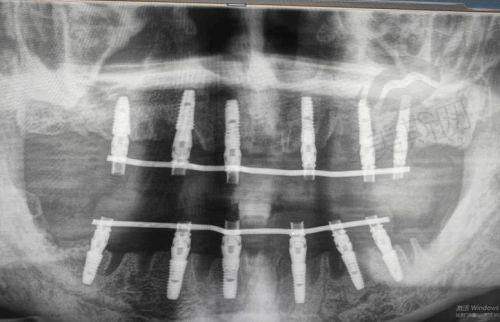

好多姊妹聽到「種植牙橋」就頭痛,其實可以簡單理解成「半種植半橋體」——缺牙位兩邊植入種植體做「支柱」,中間用牙橋連接,比起每隻牙都種植體(全種植)慳咗種植體數量,又比傳統固定橋(要磨鄰牙)更護牙。

打個比方:如果缺咗3隻連續牙,全種植要3隻種植體,而種植牙橋可能只需要2隻(兩邊各1隻),中間用橋體連接,費用慳咗成3成!但記住,呢個方法要鄰牙夠健康,牙骨條件都唔可以太差,否則支柱唔穩,後期容易鬆動。

技術特色:用AI 3D模擬種植成效(術前可以睇到種完之後啲牙點樣,香港都少有呢個技術),全口種植係強項,但種植牙橋实例相對少啲。